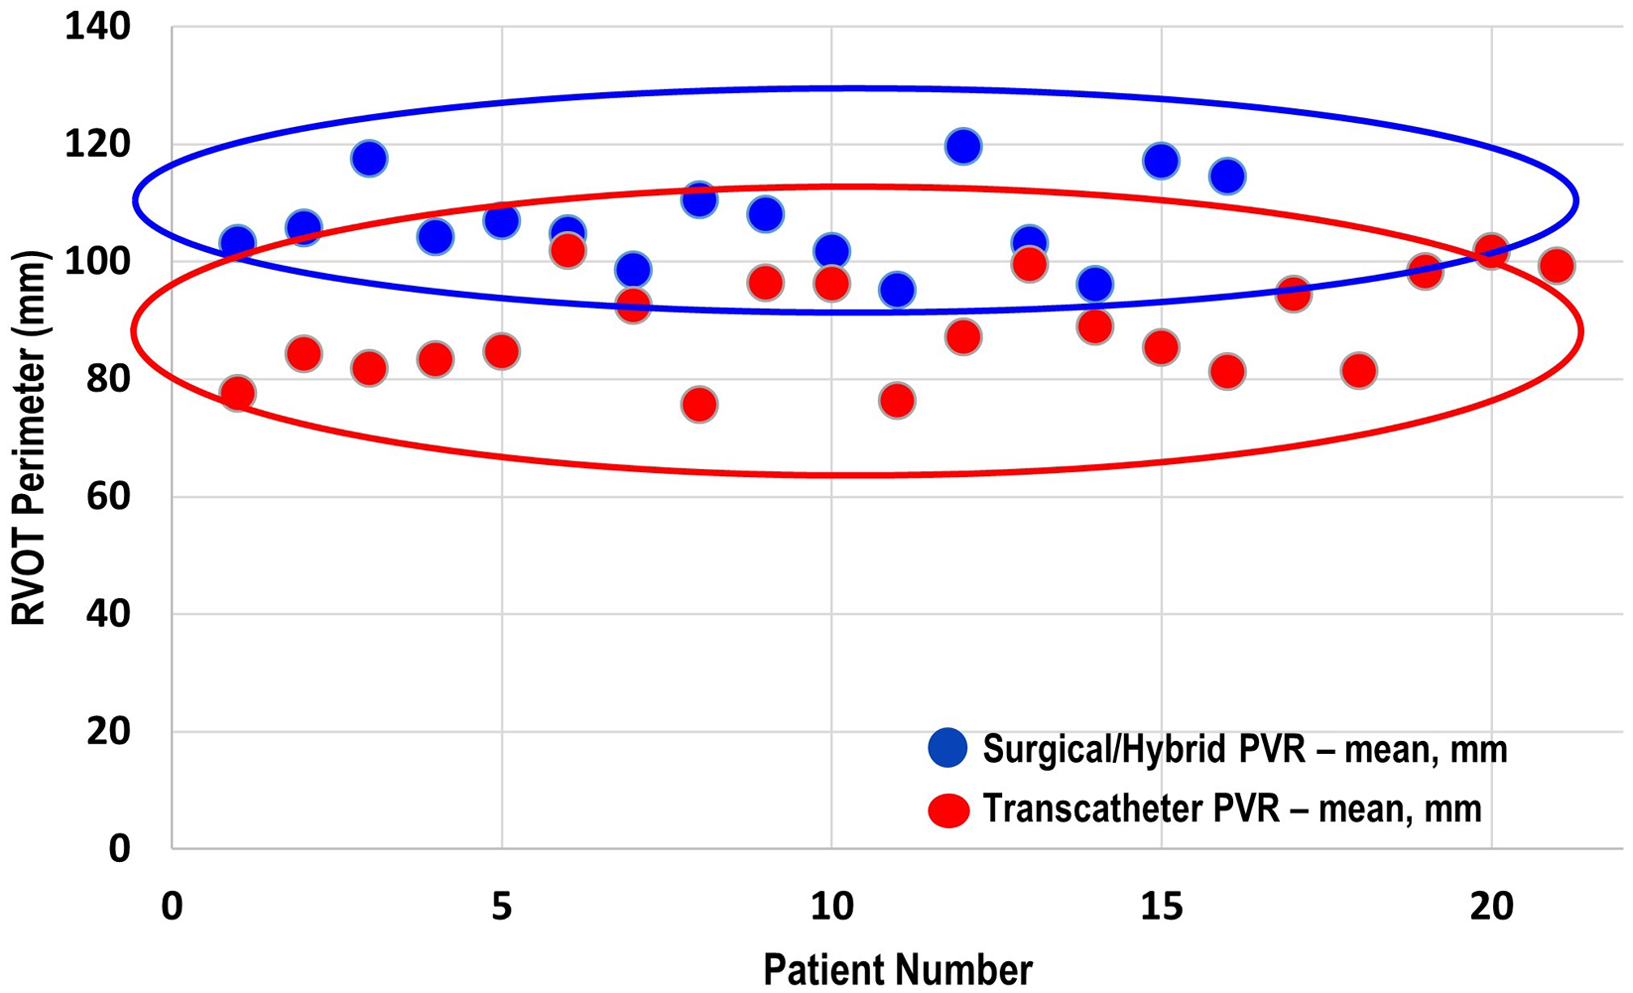

There were three patients (all within the transcatheter cohort) that did not have the non-contrast steady-state free-precession magnetic resonance angiography available, and the Twist sequence was utilised. The mean landing zone perimeter of the transcatheter cohort was 88.9 ± 8.7 mm and in the surgical/hybrid cohort measured 106.6 ± 7.5 mm (Fig 2). The two-dimensional diameter measurements from the same identified intended valve site within the transcatheter cohort were median 24.7 mm (range 19.9–27.2) in the smaller dimension and 31.3 mm (27–38.1) in the larger. For the surgical/hybrid cohort, this was 26.3 mm (22.5–33.1) and 39.7 mm (36.2–48.6), respectively. For the transcatheter cohort, the median “circularised” diameter derived from the MRI perimeter measurement (divided by π) was 27.7 mm (range 24.3–32.4). Notably, this correlated (r = 0.93, p < 0.01) with the median diameter of the narrowest region during actual transcatheter landing zone balloon sizing (lateral imaging) of 27.1 mm (range 23.2–30.1) (Fig 3). After transcatheter valve implantation, the mean outer diameter of the implanted prosthesis was 26.7 ± 2.2 mm. In comparison, the median circularised diameter based on the MRI-perimeter in the surgical/hybrid cohort was 33.5 mm (range 30.3–38).

Figure 2. Mean end-systolic right ventricular outflow tract perimeter (derived from cardiac MRI) of the surgical/hybrid palliation cohort (blue) versus the transcatheter cohort.

Given the vast array of right ventricular outflow tract morphologies necessitating pulmonary valve replacement, Reference Schievano, Capelli and Young18-Reference Schievano, Coats and Migliavacca21 calculating perimeter may prove more clinically beneficial than traditional measurements such as two-dimensional diameters. As outlined above, no transcatheter pulmonary valve replacement patient demonstrated a landing zone perimeter larger than 101.8 mm (circularised diameter 32 mm), and no surgical/hybrid patient had one smaller than 95.1 mm.

Candidacy for transcatheter pulmonary valve replacement is determined by a litany of considerations including landing zone morphology, distensibility/compliance of the landing zone, and risk of coronary artery compression. Unfortunately, no one advanced imaging technique will definitively answer all the above factors when taken in isolation. Therefore at our centre, we have generated an institutional systematic approach to pulmonary valve replacement. Reference Ligon, Latson and Ruzmetov13 This entails MRI (CT if not a candidate), which includes calculation of landing zone perimeter/circularised diameter and close examination of coronary artery proximity to the landing zone in order to best counsel the patient and/or family. The patient will then come to the cardiac catheterisation laboratory for landing zone balloon sizing and coronary artery compression testing. The landing zone perimeter has proven to be a valuable advanced imaging parameter to assist in stratifying patients into categories of potential candidates for balloon expandable transcatheter pulmonary valve replacement versus need for other methodologies. That is, patients with a large landing zone by advanced imaging (landing zone perimeter approximately greater than or equal to 98 mm or circularised perimeter of about 31 mm) are not considered candidates for traditional balloon-expandable transcatheter valve replacement. As demonstrated in Fig 2, there is certainly overlap of these populations that guides our interventional team significantly in regard to patient counseling and our heart centre in regard to multidisciplinary consensus recommendations. If transcatheter pulmonary valve replacement is not technically feasible, then consideration to hybrid off-pump plication (without cardiopulmonary bypass) or standard on-pump surgical pulmonary valve replacement is undertaken in a multidisciplinary fashion – with the preference being on the former.